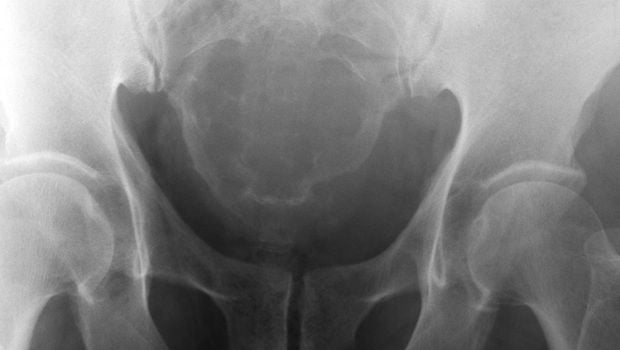

A daganat a szervezet maradandóan megváltozott sejtjeiből felépülő kóros szövetburjánzás. Növekedése a kiváló ok megszűnte után is folytatódik. A daganat nem illeszkedik be a szervezet egységébe, sőt bizonyos mértékben független a szervezet élettevékenységétől.Ha a daganat szövete az eredeti szövethez hasonló, homológ, ha eltér az anyaszövettől, heterológ daganatról beszélünk.A daganatsejt a véráram útján primer kiindulási helyétől távol is megtelepedhet, és ott áttétet adhat.A jóindulatú daganatok lassan növekszenek. Növekedésük helyhez kötött, a szervezetben szétterjedésre nem hajlamosak, áttétet nem adnak. Sejtjeik az anyaszövethez hasonlóak.A rosszindulatú sejtburjánzás megnevezése a tumor alapszövet sejtjei alapján történik.A jóindulatú csontdaganatok elhelyezkedésük és szövettípusok szerint különbözőek. A nem ossifikálódó csont fibróma kötőszövet-alapú, többnyire a csonthártya kötőszövetéből kiinduló daganat. A csont a tumor területén felpuhul. A tumor elsősorban gyermek- és fiatalkorban gyakori. Rendszerint a combcsontban vagy a csípőcsonton alakul ki.A tumor fájdalmat nem okoz, területén azonban külső erőbehatás nélküli törés alakulhat ki.Kizárólag az állkapocs-csontban képződő, kötőszövet alapú daganat. A kötőszövet csontos elemeket is tartalmaz, elcsontosodik. Az érintett helyen kemény duzzanat képződik. A tumor elsősorban gyermek- és ifjúkorban jelentkezik.OsteomaAz osteoma a környezetétől élesen elhatárolódó, csontszövetes alapú daganat. Rendszerint a koponyacsontokon és az orrmelléküregekben keletkezik. Főként felnőttkorban jelentkezik. Az osteoma elhelyezkedésének és nagyságának megfelelően különböző tüneteket okozhat. Például fejfájás, látás- és halláskárosodást, bénulást.A jóindulatú osteoblastoma viszonylag ritka. Rendszerint a csigolyákból indul ki, jóllehet bármely csonton létrejöhet. Elsősorban gyermek- és ifjúkorban jelentkezik, tíz-húsz éves kor között. Ha a tumor összenyomja a gerincvelőt, súlyos fájdalmat, idegrendszeri tüneteket, érzészavart, mozgáskiesést, bénulást okozhat.Osteoid osteomaAz osteoid osteoma az osteoblastomához hasonló daganat. A csöves csontokban növekvő daganat mérete általában nem haladja meg a két centimétert. Rendszerint gyermekkorban jelentkezik.ChondromaA chondroma viszonylag gyakori, porcszövetalapú daganat. Bármely csonton kialakulhat. Növekedése lassú, panaszokat csak a nagyméretű, rossz helyen növekvő daganat okoz. Az ideget, eret nyomó tumor súlyos szövődményeket okozhat.Chondromixoid fibrómaA nyákos kötőszövetes és porcos alapú chondromixoid fibróma a csöves csontokon, főként a combcsonton, a sípcsonton és a szárkapocs-csonton növekszik. Elsősorban fiatalkorban jelentkezik.ChondroblastomaPorszerű szövetből és meszes lerakódásokból áll. A csontok ízületi végein, általában a felkaron, a térden és a csípőn képződik, főként fiatalkorban.Juvenilis csontcisztaA hosszú csöves csontok végén, főként a térden fejlődő daganat. Általában a növekedési időszakban alakul ki. Fiúknál gyakoribb, mint lányoknál.Aneurizmás csontcisztaA hosszú csöves csontok végén, vagy a csigolyatestekben kialakuló üregrendszer. A csigolyák károsodása idegrendszeri tüneteket, bénulást okozhat.A csontdaganat röntgenvizsgálattal és a daganatból vett szövetminta kórszövettani vizsgálatával diagnosztizálható. A tumor típusa a szövettani lelet alapján határozható meg.A jóindulatú daganatok műtéti úton eltávolíthatók. Ha a daganat idegrendszeri károsodást nem okozott, a gyógyulás maradéktalanul.